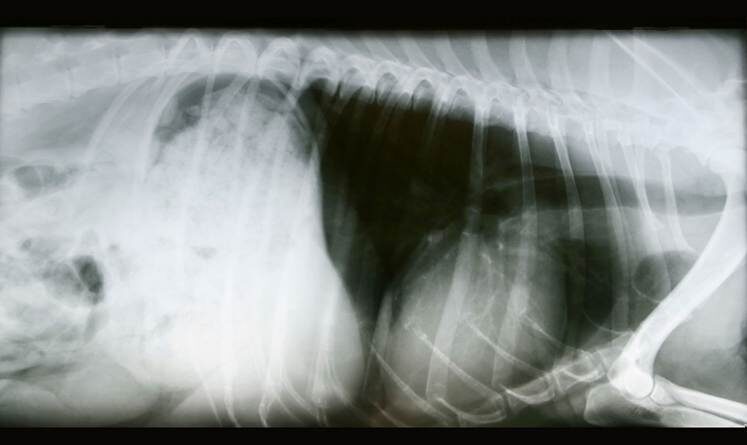

Сердце — главная боль современного добермана. Дилатационная кардиомиопатия может годами не проявляться, а потом просто выключить собаку. Добавим проблемы со свёртываемостью крови, позвоночник, онкологию. Картина получается неприятная.